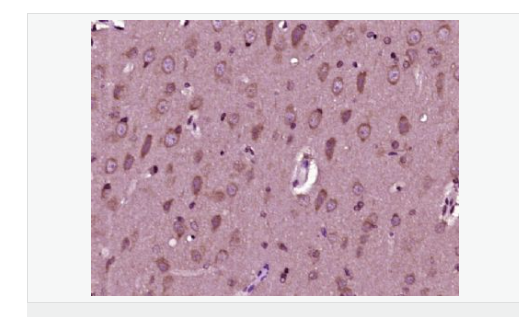

| 产品应用 | WB=1:500-2000 ELISA=1:5000-10000 IHC-P=1:100-500 IHC-F=1:100-500 ICC=1:100-500 IF=1:100-500 石蜡切片需做抗原修复 not yet tested in other applications. optimal dilutions/concentrations should be determined by the end user. |

| 细胞定位 | 细胞核 细胞浆 |